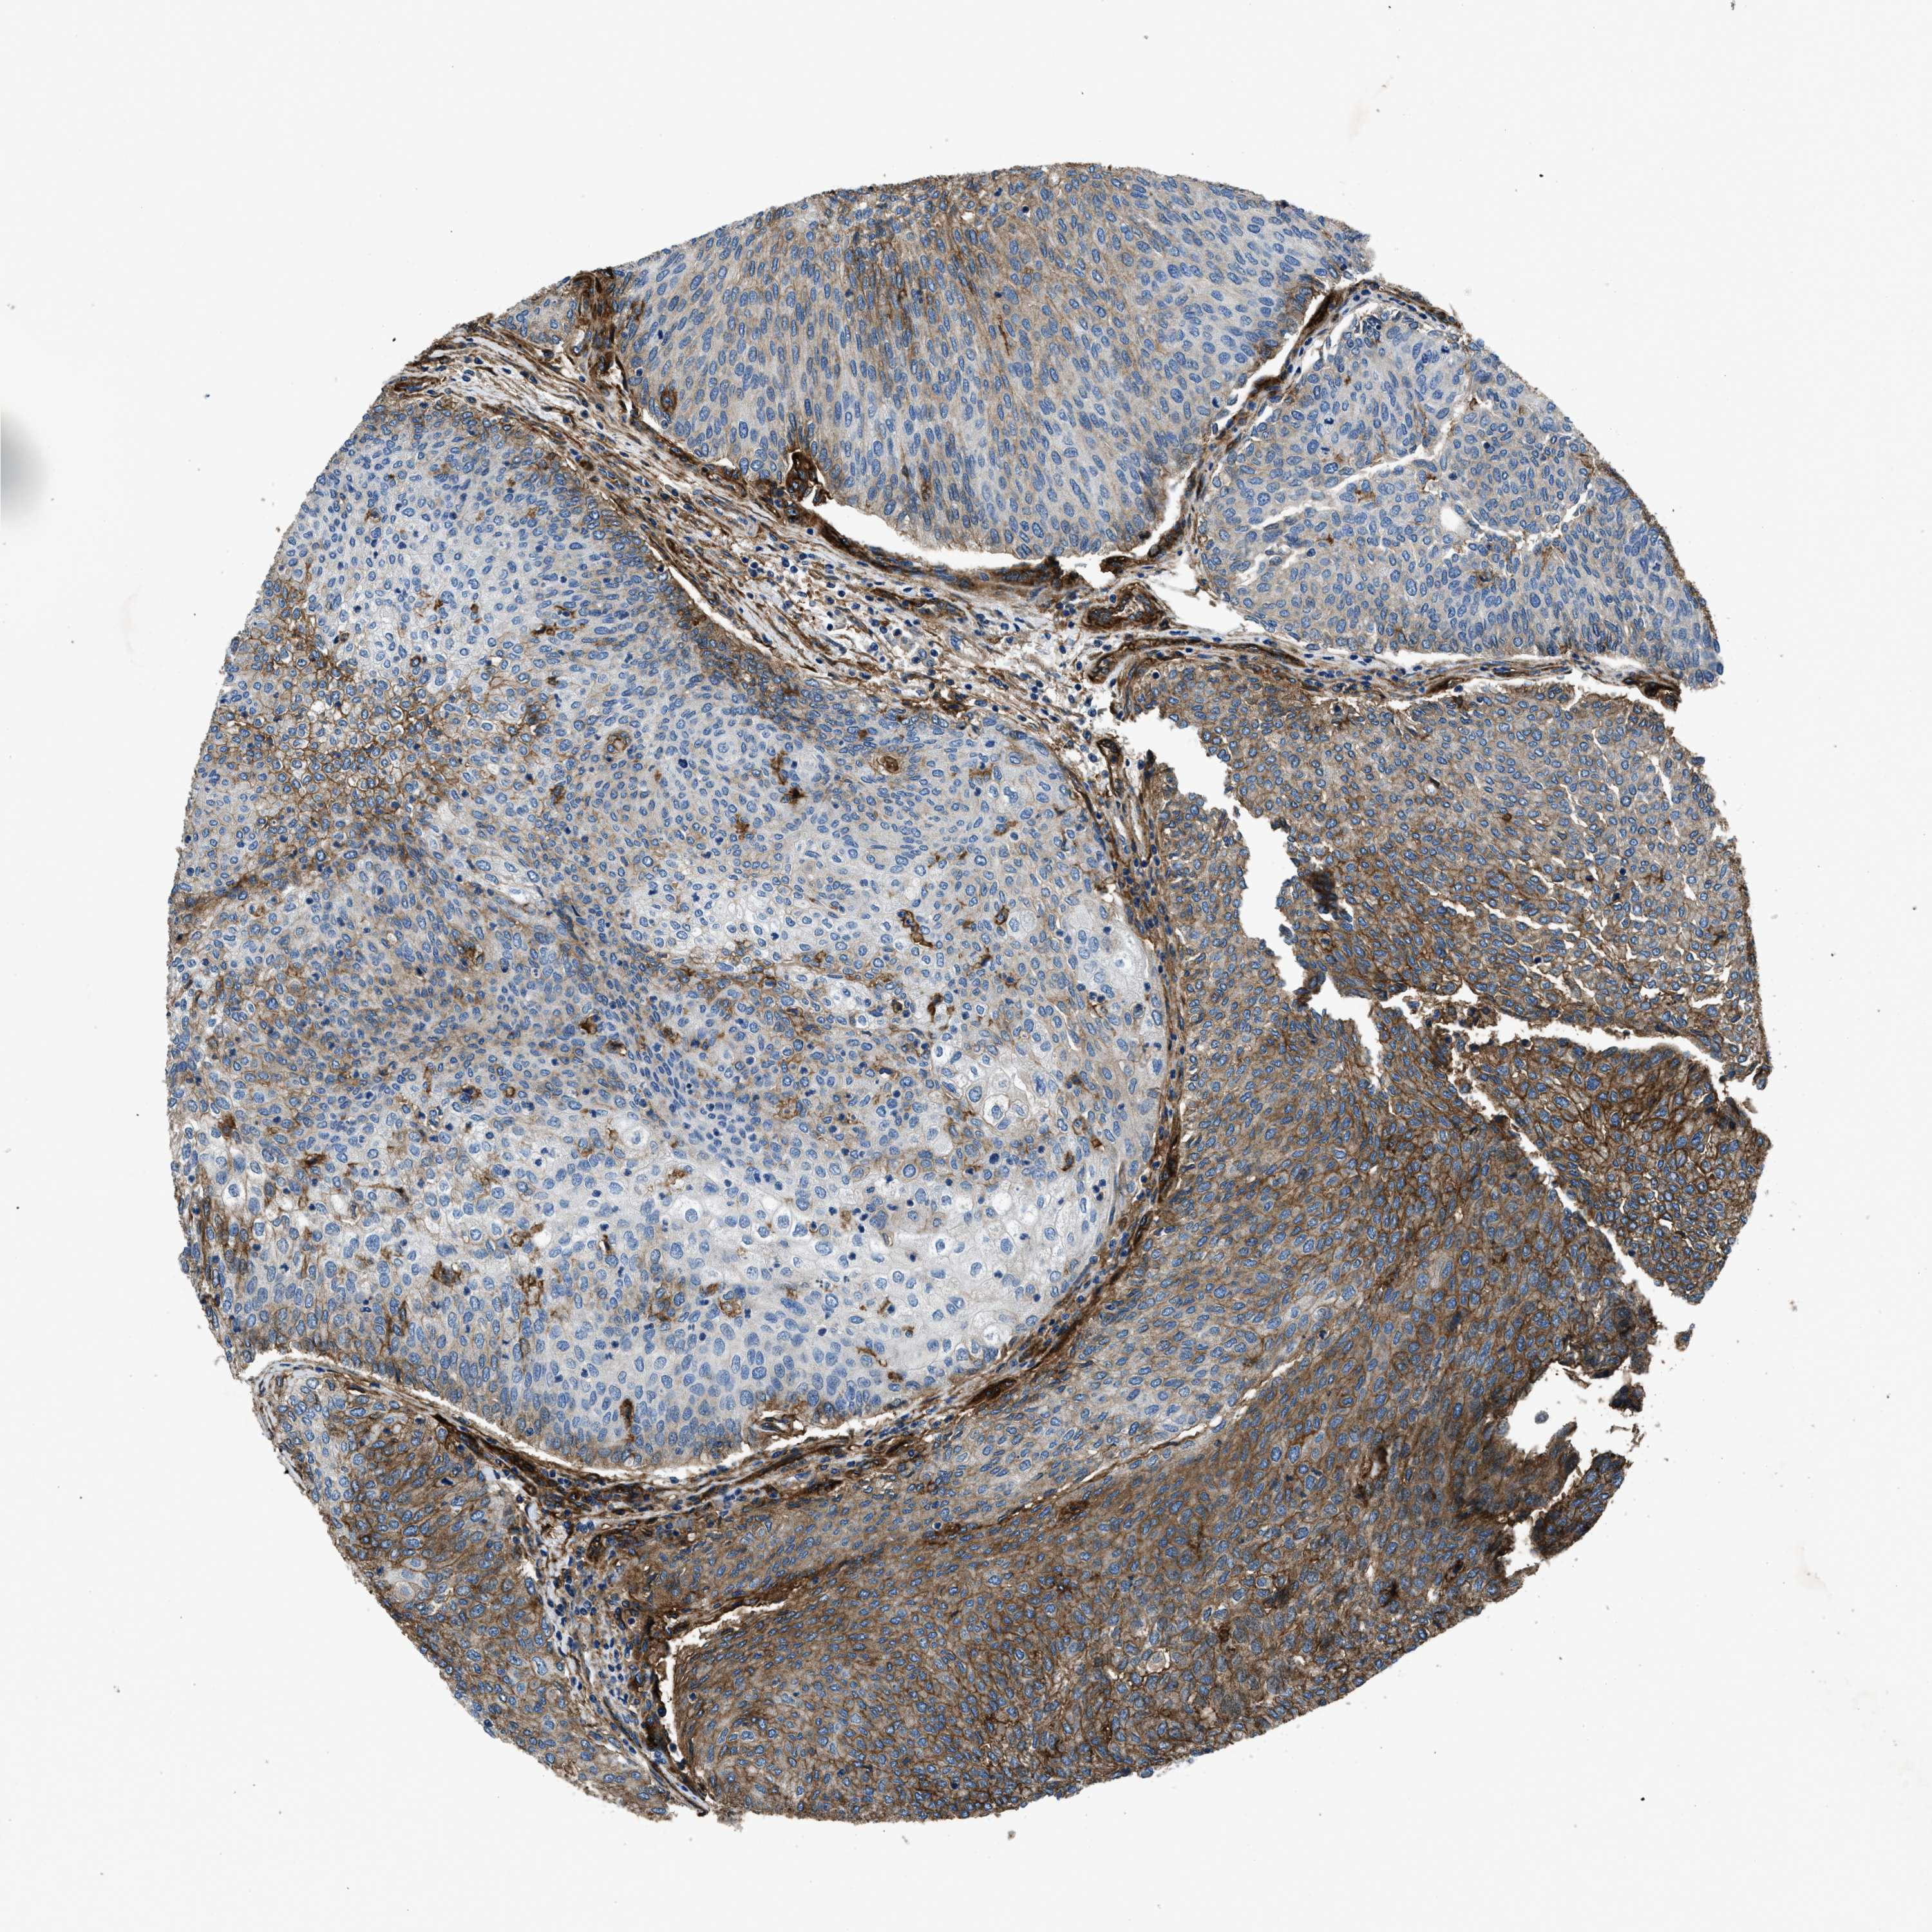

UROTHELIAL CANCER - Protein expressioni

A mouse-over function shows sample information and annotation data. Click on an image to view it in a full screen mode. Samples can be filtered based on level of antibody staining by selecting one or several of the following categories: high, medium, low and not detected. The assay and annotation is described here.

Note that samples used for immunohistochemistry by the Human Protein Atlas do not correspond to samples in the TCGA dataset.

Antibody stainingi

Antibody staining in the annotated cell types in the current human tissue is reported as not detected, low, medium, or high, based on conventional immunohistochemistry profiling in selected tissues. This score is based on the combination of the staining intensity and fraction of stained cells.

Each image is clickable and will lead to virtual microscopy that enables deeper exploration of all samples and also displays staining intensity scores, fraction scores and subcellular localization as well as patient and tissue information for each sample.

Antibody HPA009285

Antibody HPA017139

Antibody CAB017826

Urothelial carcinoma, Low grade

Urothelial carcinoma, High grade